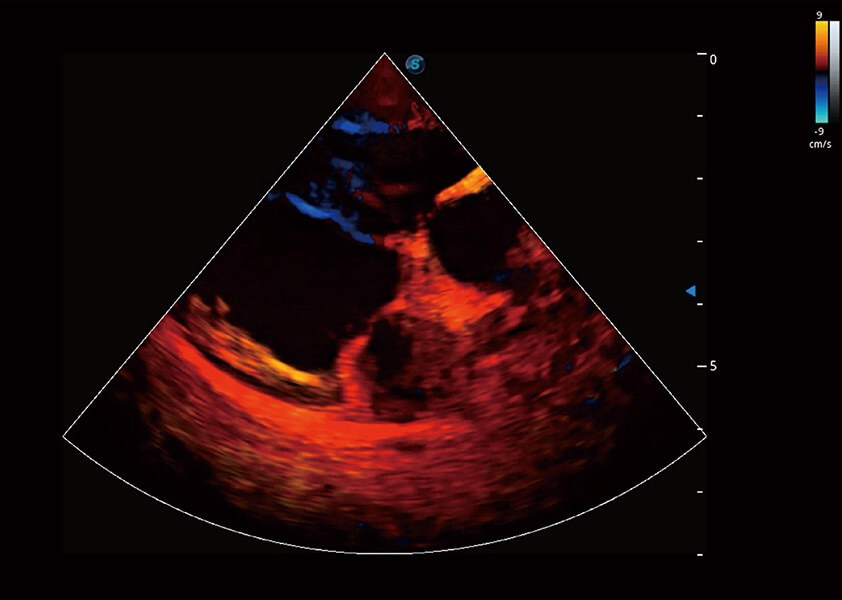

优异的基础图像

(猫)髂动脉血流频谱